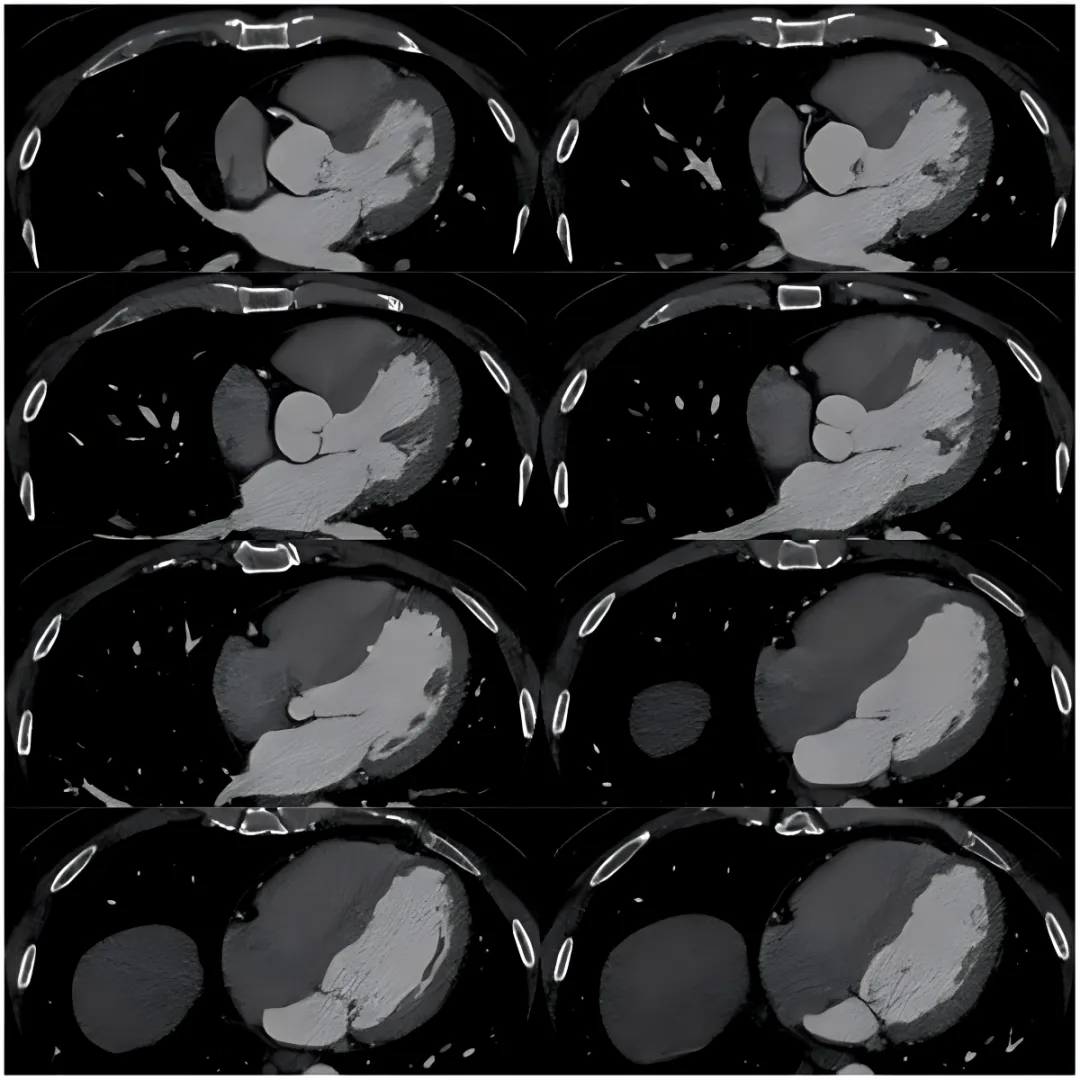

我关掉AI处理后的图像,打开了原始薄层数据,一帧一帧地看。

从左前降支开始,右冠状动脉,然后左回旋支。

看到左回旋支中段时,我的鼠标停住了。

那里有一个黑黑的、低密度的影子,附着在血管壁上——典型的非钙化性斑块。而这个斑块,已经把血管腔几乎堵死了。

原始图像

再看远端,左回旋支的远段血管居然还能显影。这只能说明一件事:有侧支循环在代偿供血。也就是说,这条血管已经闭塞了,但身体自己“绕了条小路”给远端供血,所以患者平时没什么感觉,一踢球,耗氧量增加,小路供不上,才出现症状。

而AI为什么没发现?

因为在AI的处理逻辑里,左回旋支远段因血流量减少、造影剂浓度低,被当成了“不存在”。AI只识别了主干近段,给出了一个“轻度狭窄”的错误结论。

人工智能图像